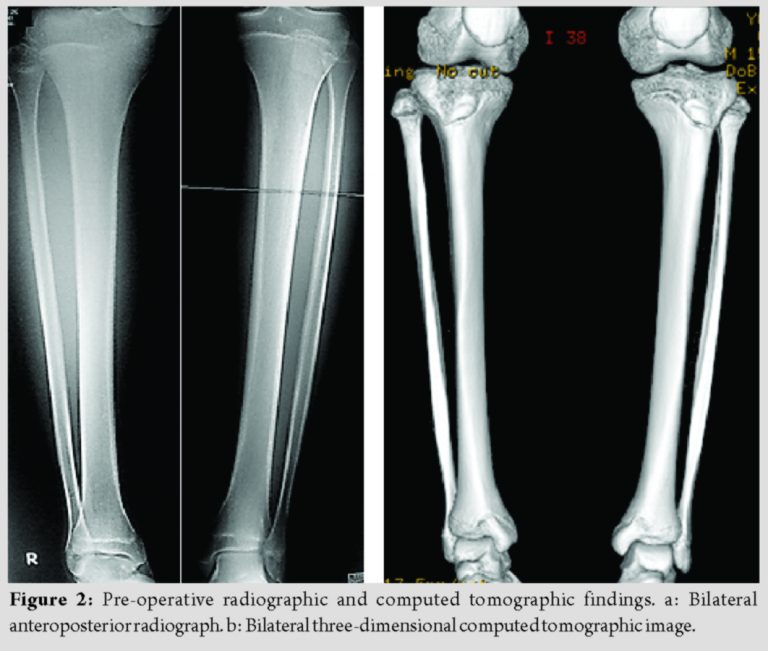

He had no leg length discrepancy at the time of surgery. His distal physis deformity as assessed by simple radiographic examination was characterized as follows: No coronal deformity, no sagittal deformity, and 31.0° external rotation. His rotational deformity as assessed by computed tomography was characterized by a tibial torsion angle of 65.6° on the right and 35.8° on the left (Fig. 2, 3).